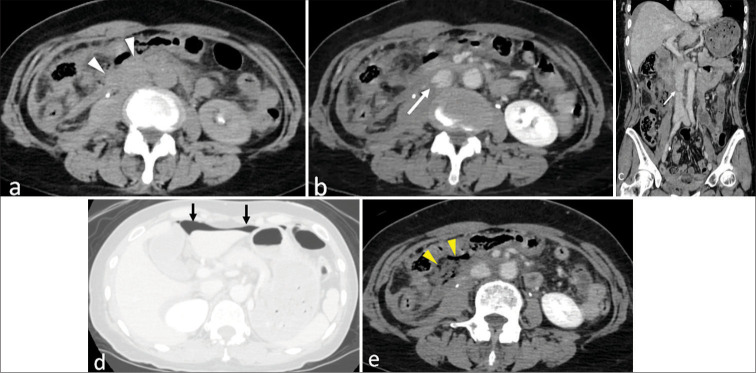

钝性外伤性下腔静脉(IVC)损伤是罕见的,提出了诊断和治疗的挑战。我们报告一例钝性外伤性下腔静脉损伤合并肠穿孔和脊髓损伤,成功地通过非手术保守治疗。一名57岁的妇女在一辆未系安全带的机动车碰撞中受伤。计算机断层扫描(CT)显示在肾下水平不规则的下腔静脉轮廓和腹膜后血肿,导致钝性外伤性下腔静脉损伤的诊断。腹腔内自由空气提示肠穿孔,磁共振成像证实C5/6脊髓损伤。这种伤害的组合可能会引起安全带伤害模式的怀疑。手术治疗肠穿孔,脊柱损伤后路固定。由于患者血流动力学稳定,下腔静脉损伤选择保守治疗。随访CT显示腹膜后血肿减少,下腔静脉轮廓改善,表明保守治疗成功。钝性外伤性下腔静脉损伤是罕见的,一些病例不表现造影剂外渗。在这个病例中,诊断是基于下腔静脉轮廓异常和腹膜后血肿。考虑到患者血流动力学稳定,选择保守治疗。仔细解读CT表现对诊断下腔静脉损伤至关重要,适当的临床判断是成功非手术治疗的关键。

Blunt traumatic inferior vena cava (IVC) injury is rare and presents diagnostic and therapeutic challenges. We report a case of blunt traumatic IVC injury associated with bowel perforation and spinal cord injury, successfully managed with non-operative conservative treatment. A 57-year-old woman sustained injuries in a motor vehicle collision with a seatbelt fastened. Computed tomography (CT) revealed an irregular IVC contour at the infrarenal level and a retroperitoneal hematoma, leading to the diagnosis of blunt traumatic IVC injury. Free intraperitoneal air suggested bowel perforation, and magnetic resonance imaging confirmed a C5/6 spinal cord injury. This combination of injuries may raise suspicion for a seatbelt injury pattern. The bowel perforation was surgically treated, and posterior fixation was performed for the spinal injury. Since the patient remained hemodynamically stable, conservative management was selected for the IVC injury. Follow-up CT revealed a reduction in the retroperitoneal hematoma and improvement in the IVC contour, indicating successful conservative treatment. Blunt traumatic IVC injury is rare, and some cases do not exhibit contrast media extravasation. In this case, the diagnosis was based on IVC contour abnormalities and retroperitoneal hematoma. Considering the patient's stable hemodynamics, conservative treatment was selected. Careful interpretation of CT findings is essential for diagnosing IVC injury, and appropriate clinical judgment is key to achieving successful non-operative management in selected cases.